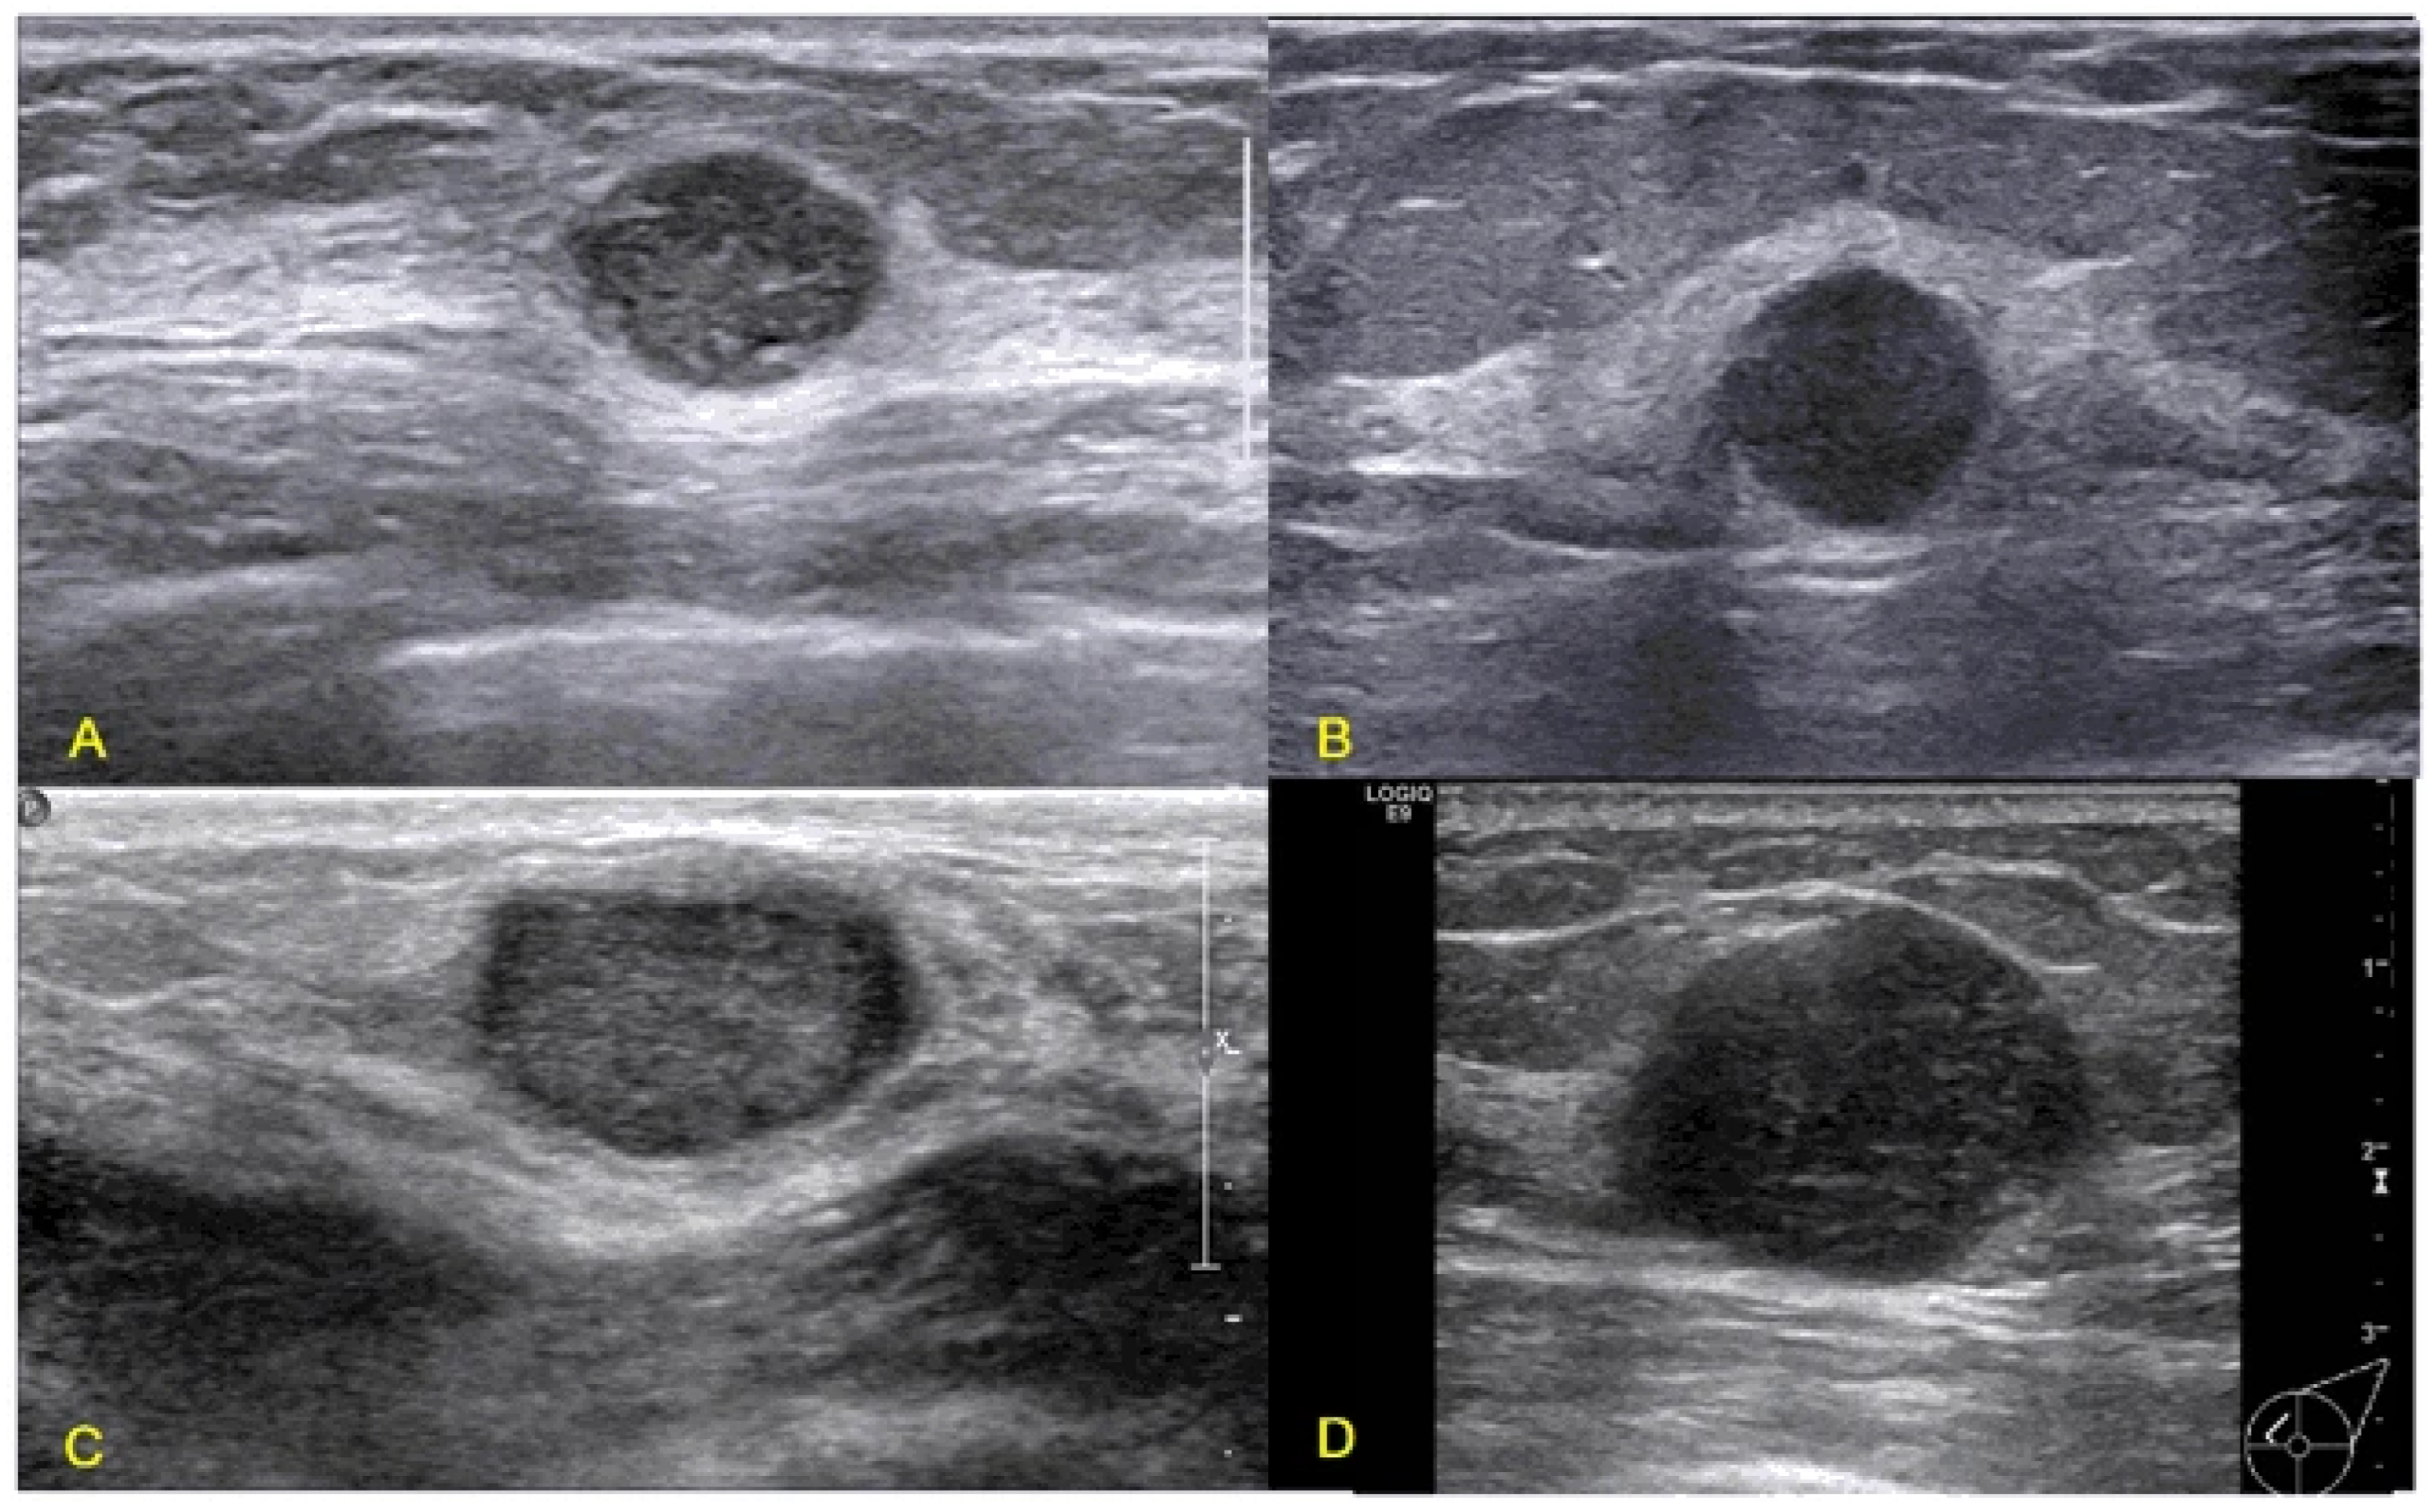

2.2. Ultrasound

- Kim, S.H.; Bo Kyoung Seo, J.L.; Kim, S.J.; Cho, K.R.; Lee, K.Y.; Je, B.K.; Kim, H.Y.; Kim, Y.S.; Lee, J.H. Correlation of ultrasound findings with histology, tumor grade, and biological markers in breast cancer. Acta Oncol. 2008, 47, 1531–1538. [Google Scholar] [CrossRef]

- Lamb, P.M.; Perry, N.M.; Vinnicombe, S.J.; Wells, C.A. Correlation Between Ultrasound Characteristics, Mammographic Findings and Histological Grade in Patients with Invasive Ductal Carcinoma of the Breast. Clin. Radiol. 2000, 55, 40–44. [Google Scholar] [CrossRef]

- Bae, M.S.; Han, W.; Koo, H.R.; Cho, N.; Chang, J.M.; Yi, A.; Park, I.A.; Noh, D.Y.; Choi, W.S.; Moon, W.K. Characteristics of breast cancers detected by ultrasound screening in women with negative mammograms. Cancer Sci. 2011, 102, 1862–1867. [Google Scholar] [CrossRef]

- Irshad, A.; Leddy, R.; Pisano, E.; Baker, N.; Lewis, M.; Ackerman, S.; Campbell, A. Assessing the Role of Ultrasound in Predicting the Biological Behavior of Breast Cancer. Am. J. Roentgenol. 2013, 200, 284–290. [Google Scholar] [CrossRef]

- Gokhale, S. Ultrasound characterization of breast masses. Indian J. Radiol. Imaging 2009, 19, 242–247. [Google Scholar] [CrossRef]

| Solid Nodule Characteristics | Positive Predictive Value |

|---|---|

| Speculation | 91.8 |

| Taller than wide | 81.2 |

| Angular margins | 67.5 |

| Shadowing | 64.9 |

| Branching pattern | 64.0 |

| Hypo echogenicity | 60.1 |

| Calcifications | 59.6 |

| Duct extension | 50.8 |

| Micro lobulations | 48.2 |